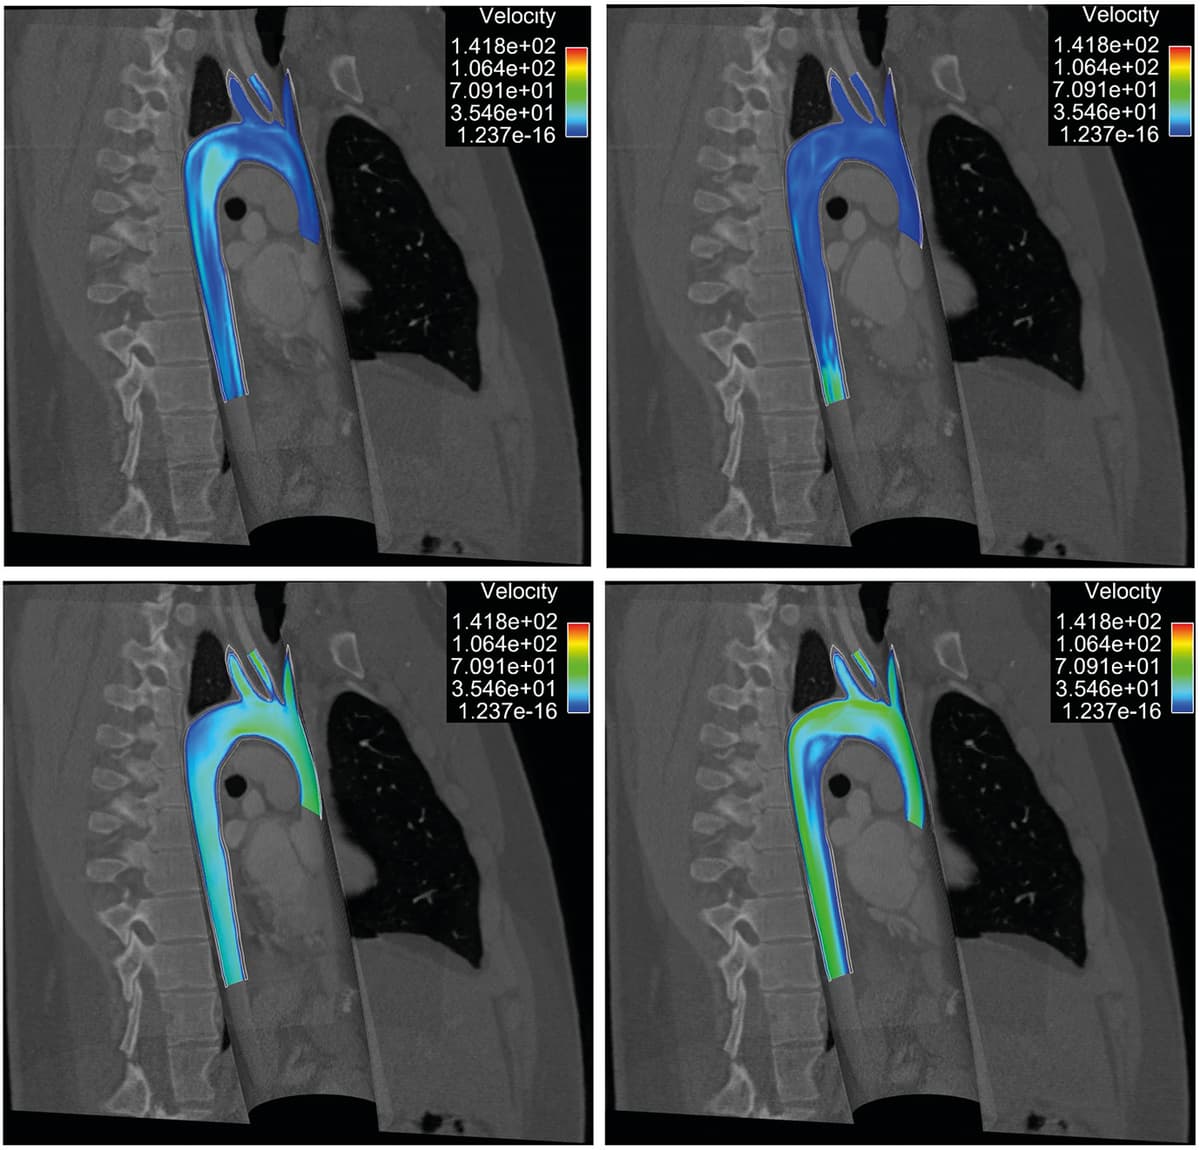

and can be made rapidly decreasing provided that and remain moderate and is taken sufficiently large. This approach has been implemented with multiple refinements by Moireau et al. [39 P. Moireau, D. Chapelle and P. Le Tallec, Filtering for distributed mechanical systems using position measurements: perspectives in medical imaging. Inverse Problems25, 035010, 25 (2009) ], comparing in-depth the displacement vs. velocity controls.

which is close to (1) when . A Bayesian approach can be used to identify the parameters from the model, as developed in [49 L. Yang, X. Meng and G. E. Karniadakis, B-PINNs: Bayesian physics-informed neural networks for forward and inverse PDE problems with noisy data. J. Comput. Phys.425, 109913, 23 (2021) ]. Lucor et al. have developed the approach for the thermo-mechanical simulation of an incompressible viscous flow [31 D. Lucor, A. Agrawal and A. Sergent, Physics-aware deep neural networks for surrogate modeling of turbulent natural convection, preprint, arXiv:2103.03565 (2021) ]; cf. Figures 5 and 6.